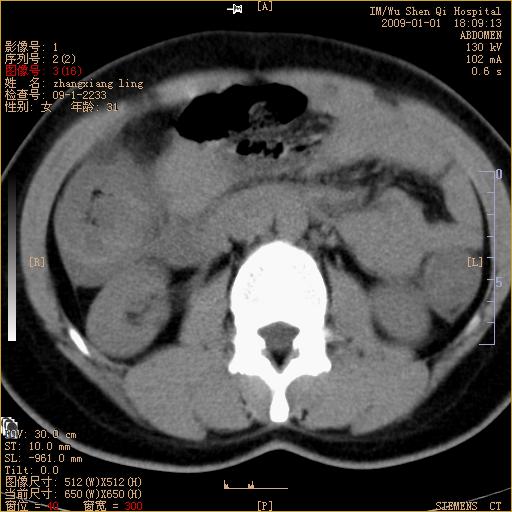

标题: CT17527:F31Y,腹痛伴血便9小时 [打印本页]

标题: CT17527:F31Y,腹痛伴血便9小时

升结肠肠壁不规则增厚,似呈同心圆改变,其有积液。结合病史首先考虑肠套叠伴肠壁坏死可能性大,结肠肿瘤待排。

升结肠肠壁不规则增厚,似呈同心圆改变,其有积液。结合病史首先考虑肠套叠伴肠壁坏死可能性大,结肠肿瘤待排。支持!(发病急,无过去史,应首先考虑:肠套叠)

结合病史并看到升结肠增粗及局限的腹腔积液,考虑肠套叠伴肠壁坏死可能性大

患者已手术,结果肠系膜血栓形成肠坏死

结果:患者已手术,结果肠系膜血栓形成肠坏死。回过头再看局部肠壁增厚有分层(高密度坏死及低密度水肿)表现。